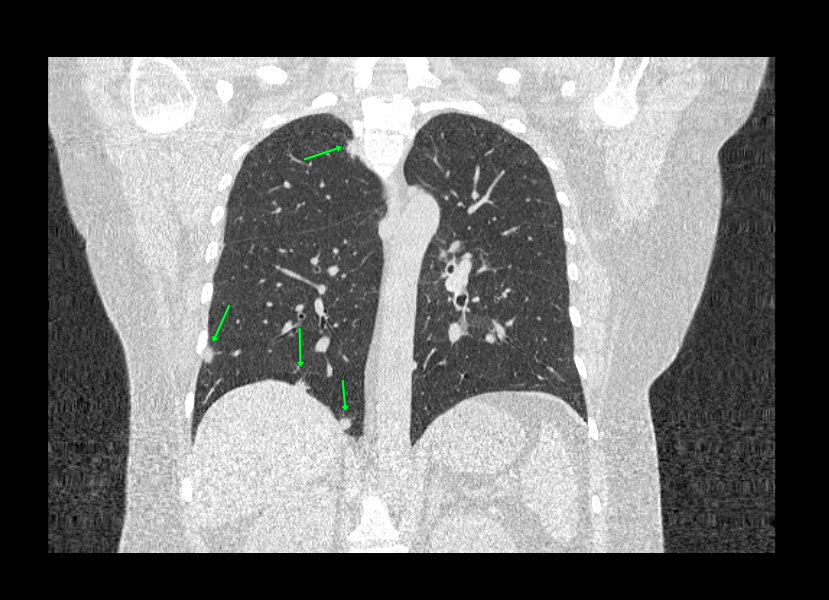

Во время исследования рентгеновская трубка томографа вращается вокруг исследуемой области и производит множество послойных снимков с шагом 0,5-1 мм. Полученные снимки поперечного сечения с помощью компьютерной программы могут быть преобразованы в 3D-изображения исследуемого органа или участка ткани. Это позволяет выявлять практически все заболевания легких на ранних стадиях и назначать своевременное лечение.

В некоторых случаях, например, при подозрении на опухолевый процесс, проводится КТ легких с контрастированием, когда для лучшей визуализации патологического очага пациенту внутривенно вводится йодсодержащий контрастный препарат. Контрастное вещество накапливается в патологических участках и обеспечивает их яркую визуализацию на фоне неизмененной ткани. С помощью контрастирования можно визуализировать кровеносные сосуды, выявить первичные опухоли и метастазы в легких, дифференцировать новообразования, например, отличить доброкачественную опухоль от злокачественной.

При проведении мультиспиральной КТ легких можно диагностировать различные заболевания, в том числе: